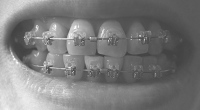

奥に引っ張るのは前歯の隙間を詰めてからにするとかなんとか言い出して、ワイヤー交換して前の歯にパワーチェーン(だと思う)を付けて終了。

しかもワイヤーをもう一段太くしようとして、ブラケットに無理やり押し込んで抜けなくなり、顎をギシギシいわせながらぐいぐい引っ張られました。以前にも同じことやってんのよね、この先生。

その後、何事もなかったようにワイヤーを付け始めたので抜けたのか?と思っていたのですが、終わってから見てみたら、刺さったワイヤーはそのままで、交換したワイヤーがブラケットに細い針金で固定されてました

まぁほんまに、ないんやろうけどなぁ。奥に引っ張るのは前歯の隙間を詰めてからにするとかなんとか言い出して、ワイヤー交換して前の歯にパワーチェーン(だと思う)を付けて終了。